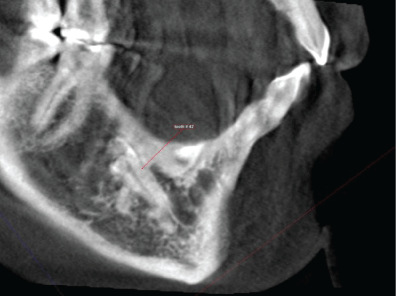

Reformatted cropped panoramic view shows that the right mandibular canine (#43) is impacted and the root is fully formed with dilacerations of the tip of the root, the crown is directed mesially (Figure 2).

Figure 2: Reformatted cropped panoramic view of the impacted mandibular right canine and lateral incisor.